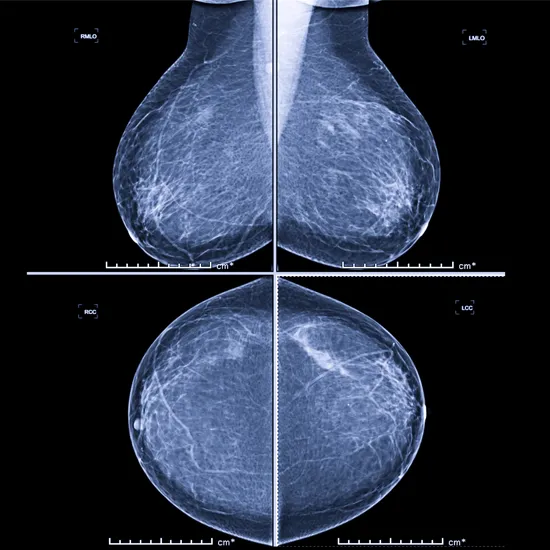

mammography x-ray both side breast

Mammography uses low-dose x-rays to identify breast cancer. This test is intended to screen females under the age of 40 for breast cancer and to diagnose it early. Women with symptoms such as a lump or soreness in the breasts or unusual nipple discharge are also recommended to consult a doctor immediately.

Mammography is an X-ray diagnostic imaging method which is used to evaluate the breast for disease, lumps and cancer.It serves as a screening and diagnostic tool. Its golden tool in early diagnosis of breast cancer.

A mammogram is a type of breast X-ray that physicians use to check for breast cancer and identify any anomalies in the breast tissue. Mammograms are thought to be a helpful test for early detection of breast cancer, even before symptoms appear. Sometimes they take up to three years to manifest or become noticeable.

Mammography examination also known as mammogram. It uses a very low dose of X-rays to examine the breast.